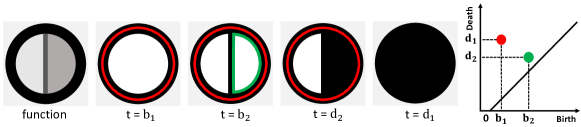

We review the basics of persistent homology in an intuitive way. Interested readers may refer to [20] for more details. Persistent homology extracts the topological information of data observed via a scalar function. Given an image domain, , and a real-valued function , we can construct a sublevel set where is a threshold controlling the “progress” of sublevel sets. The family of sublevel sets defines a filtration, i.e., a family of subsets of nested with respect to the inclusion: if . As the threshold increases from to , topological structures such as connected components, handles, and voids appear and disappear. The birth time of a topological structure is the threshold at which the structure appears in the filtration. Similarly, the death time is the threshold at which the structure disappears. Persistent homology tracks the topological changes of sublevel sets and encodes them in a persistence diagram, i.e., a point set in which each point represents a topological structure with birth time and death time . Its lifespan, i.e., , is called the persistence of the structure. In practice, we believe persistence is an indicator of the saliency of a topological structure; it has been proven that the persistence of a structure bounds the amount of perturbation one has to inject into the input in order to “shed off” the structure [14]. One may compute the number of linearly independent topological structures at different thresholds, . These counts parametrized by constitute a simpler topological signature called Betti curves. We acknowledge that while Betti curves can be directly computed from the persistence diagram, the reverse is not possible.

See Fig. 4 for an example function and its sublevel sets at different thresholds. At time , a new handle (delineated by the red cycle ) is created. This handle is later destroyed at time . Another handle delineated by the green cycle is created and killed at and respectively. The topological changes are summarized in a persistence diagram on the right. Each handle corresponds to a 2D dot in , whose and coordinates are birth and death times. Their persistence values are and respectively.

Next, we formally introduce how different topological structures can be represented with cycles. We also explain how these representative cycles are computed. Intuitively, a topological cycle of dimension is a -manifold without boundary. A 1-dimensional (1D) cycle is a loop. A 2-dimensional (2D) cycle is a bubble. A cycle represents a persistent homology structure if it delineates the structure at its birth. For example, in Fig. 4, the red and the green loops denote the handles born at time and , respectively.